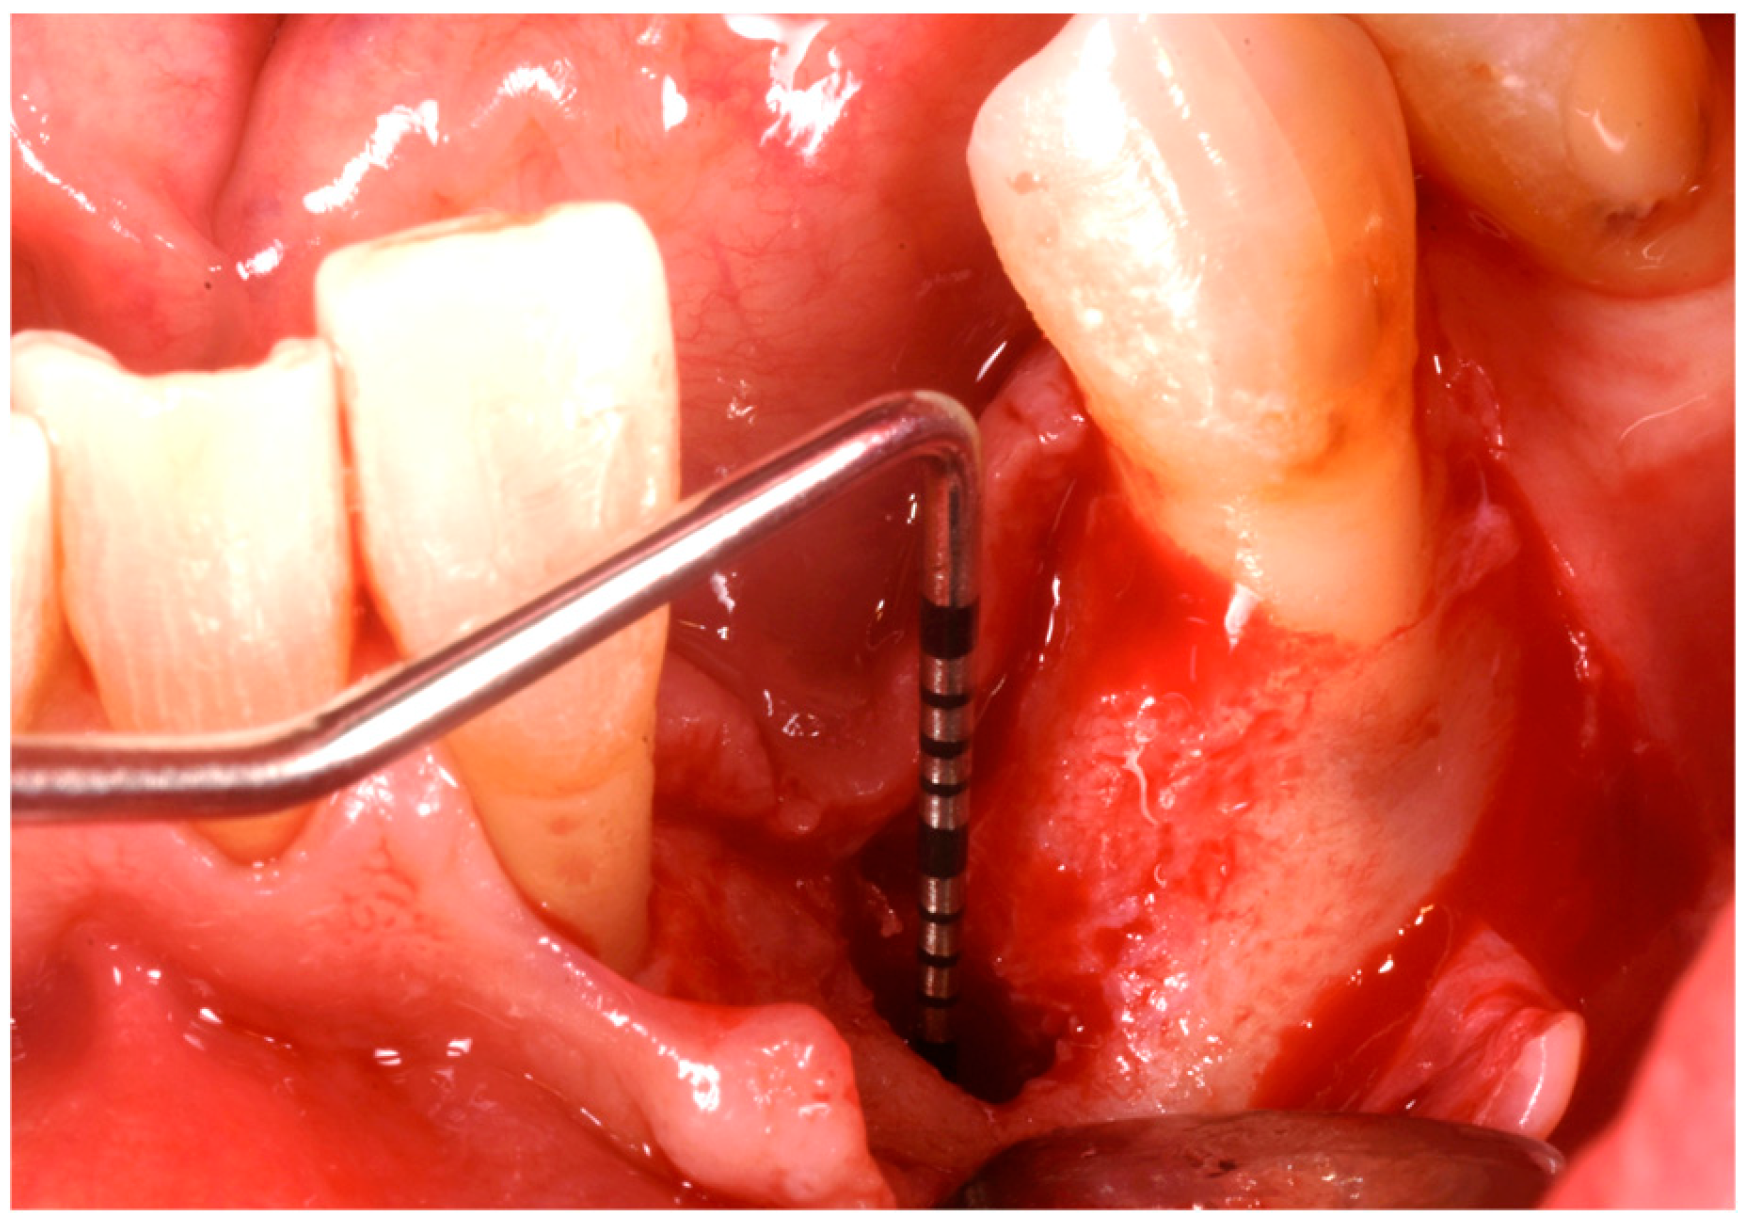

3. Surgical Technique and Case Presentation (Patient N° 3)

3.2. Hard Tissue Augmentation

3.3. Implant Insertion and Follow-Up